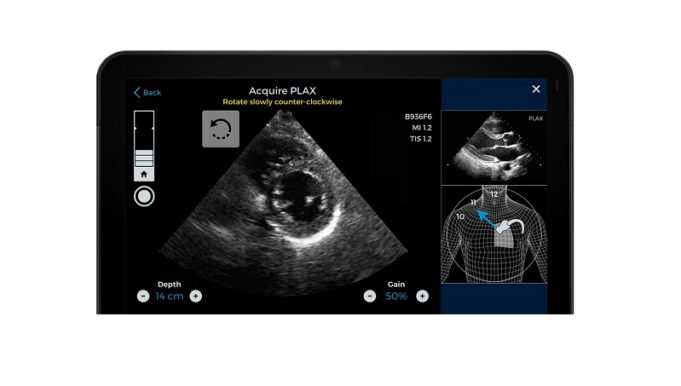

Royal Philips has announced that it has received 510(k) clearance from the US Food and Drug Administration (FDA) to market a wide range of its ultrasound solutions for the management of COVID-19-related cardiac and lung complications.

Handheld and portable ultrasound...

The US Food and Drug Administration (FDA) has expedited clearance of an update to software from Caption Health, a medical artificial intelligence (AI) company, that is designed to aid frontline healthcare workers to perform diagnostic-quality cardiac ultrasounds.

Following a...

The US Food and Drug Administration (FDA) has authorised marketing of software to assist in the acquisition of cardiac ultrasound, or echocardiography, images. The software, called Caption Guidance (Caption Health), is an accessory to compatible diagnostic ultrasound systems and...